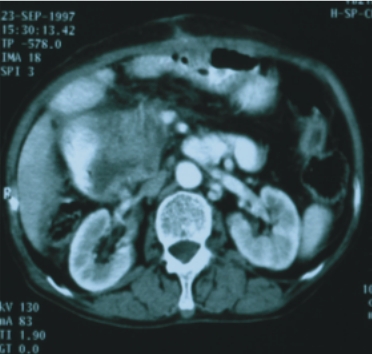

56歲/男性 (肝癌合併後腹腔淋巴腺轉移) |

74歲/男性 (直腸癌合併後腹腔淋巴腺轉移) |

||

| 90/5/2

(治療前) |

90/6/30(治療後) |

90/8/16(治療前) |

90/12/21(治療後) |